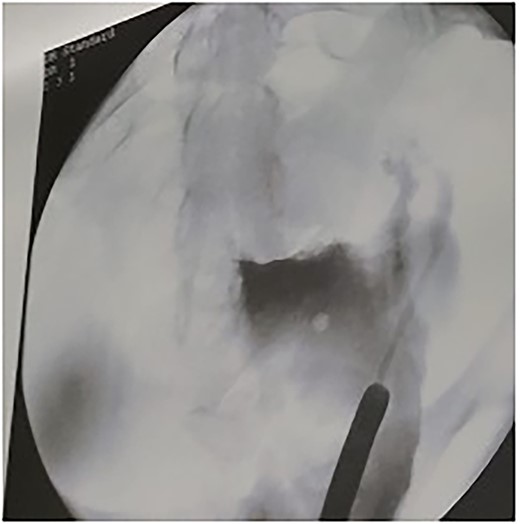

The patient tolerated the procedure very well and was transferred to the recovery room in stable condition. We did inform the patient that there is a small likelihood of developing a fistula within 2 weeks post-operatively. The patient did well in the post-operative period, recovered and was discharged to home in a stable condition. Unfortunately, on day 8, post-operatively, she started to have a leakage of urine per vagina. She was admitted for investigation, a CT Urogram was done with delayed images that confirmed the diagnosis of ureterovaginal fistula. The urologist was involved and consulted at this point; the plan was to take the patient for cystoscopy with retrograde ureteroscopy. Ureteroscopy wth retrograde fluoroscopy showed evidence of a ureterovaginal fistula (Figs 4 and 5) in which a DJ stent was inserted successfully (Fig. 6). The patient was explained about the post-operative course and plan. We decided to keep the stent for 12 weeks and then re-assess. The patient was covered by prophylaxis low-dose nitrofurantoin single daily dose of 100 mg. Fortunately, the leakage decreased gradually until it stopped. The patient was taken to the operating room to re-assess the fistula by cystoscopy and retrograde fluoroscopy. Retrograde fluoroscopy confirmed that the fistula healed. The stent was removed, and the patient was discharged to home in a stable condition.